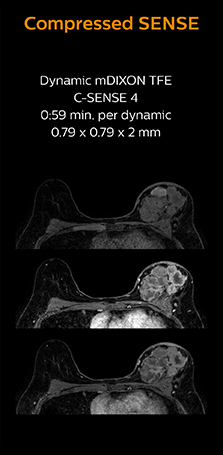

3D MRI with Compressed SENSE of patient with breast cancer

This patient underwent MRI on Ingenia 1.5T with Compressed SENSE. Compressed SENSE was used to reduce the scan time in order to decrease the time that the patient may experience discomfort and pain, both of which may lead to patient motion. The 3D BreastVIEW and 3D high resolution mDIXON images – both mDIXON contrasts are acquired in the same exam – show high quality images even with the shorter scan time. The spatial resolution of the dynamic scan with Compressed SENSE is higher than in the previous protocol (not shown) which allows for better visualization of the lesion with respect to the muscles of the thoracic wall and better delineation of small structures.

For breast imaging, a fast, high resolution scan can be important for a female patient having to lie in an uncomfortable, face-down position in the scanner. Compressed SENSE also helps us to obtain higher1 quality images using 3D BreastVIEW and 3D high resolution mDIXON sequences in the same examination time as in our previous exam protocol.